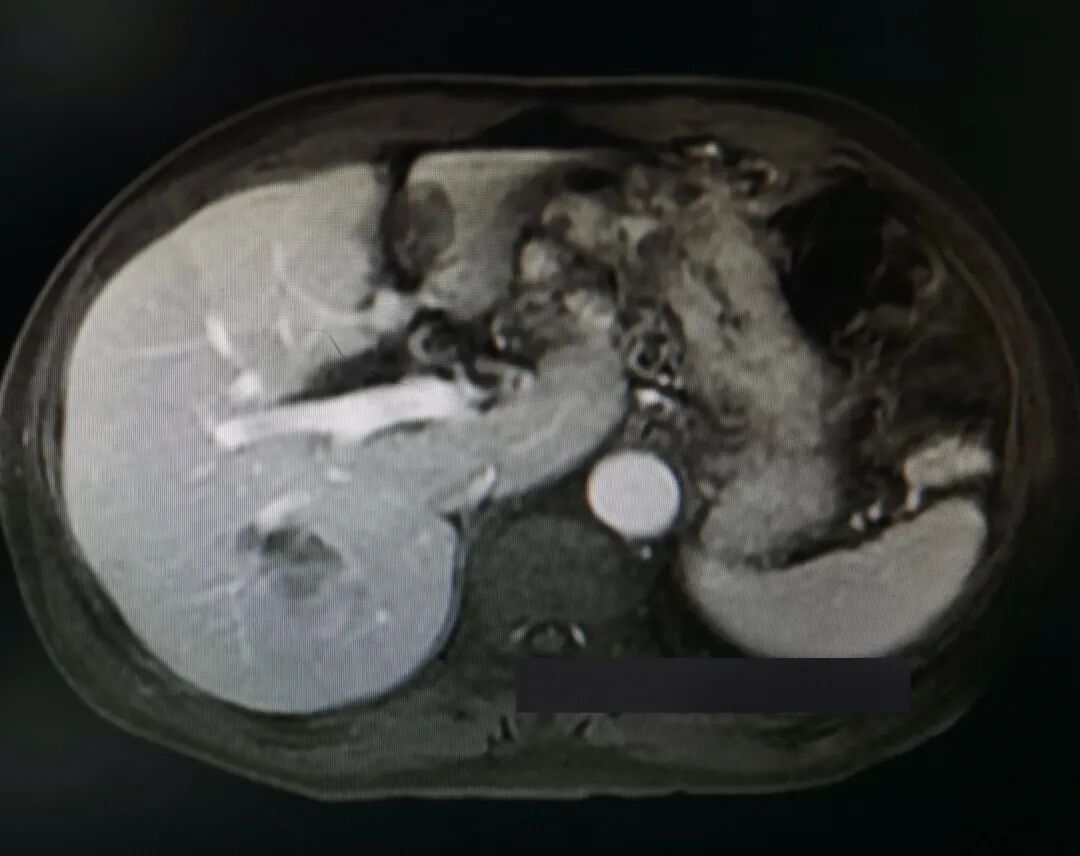

予以酪氨酸激酶抑制剂(TKI) PD-1免疫检查点抑制剂治疗计3个月,其间行两次TACE介入治疗。复查甲胎蛋白下降至26 ng/ml,增强核磁影像提示病灶坏死、缩小、部分子灶消失,较大者位于右后叶右尾状叶,大小12×9 cm,仍见残留多发活性(影像如图2所示)。

图2.转化后核磁影像(滑动浏览)